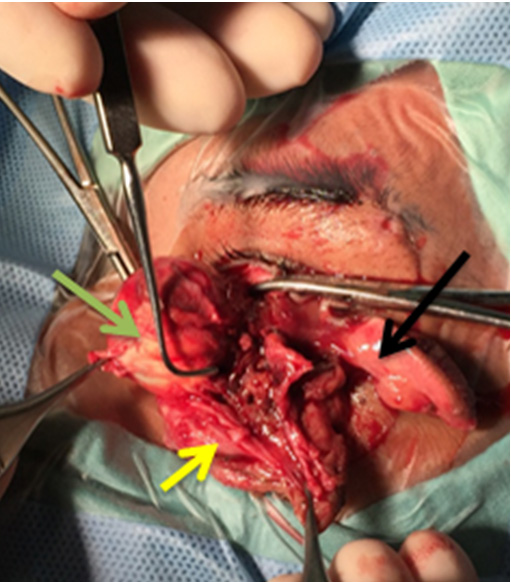

A 19-year-old male presented to the emergency room. The patient met with a motor cycle accident seven days prior to admission. He was using a helmet without a face cover. He was found with the gear shift of the motorcycle which is present in the foot area, embeded below the eye into the socket and he had to be pulled away from it. At the emergency room, he was conscious with a GCS of 15/15. On physical examination the left eye was positioned outside the eyelid fissure, hanging by an array of tissues that seemed to be superior and inferior oblique muscles as well as orbital fat (Figure 1). The inferior palpebra was lacerated full thickness and hanging by the temporal canthus (Figure 2).

The patient underwent surgery. Exploration was done under general anestesia and then enucleation was done due to the improbability of repositioning the eyeball and no possibility of recovering visual function. Before the procedure, further examination was done to evaluate the extent of the trauma. It was found that the rectus muscle was released entirely from the globe except for the superior and inferior oblique muscles. The optic nerve was avulsed at 20 mm posterior to the globe (Figure 4). There was a full thickness wound horizontally in the posterior portion of the globe lateral to the optic nerve which causes the globe to become hypotonous.

Figure 3: Photograph during sugery. Supra-cillia shown with blue arrow. Full thickness laceration of the superior lid (black arrows). Full thickness laceration of the inferior lid (yellow arrow). The globe moved nasally (green arrow).